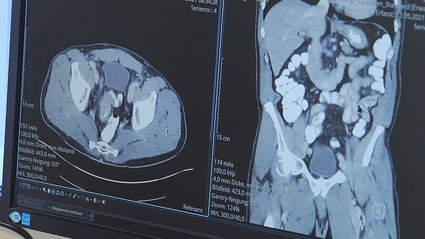

Prof. Dr. Karl-Heinz Dietl, der Chefarzt der Allgemeinchirurgie in Weiden und Tirschenreuth, spricht sogar von vielen Kollateralschäden. Besonders im onkologischen Bereich seien viele Patienten zu spät gekommen. Dadurch würden die Chancen auf eine vollständige Genesung oder aber auch die Überlebenschancen sinken.